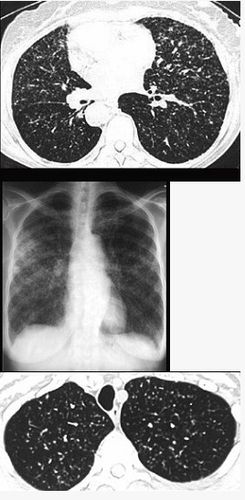

肺结核咳痰带血丝图片,肺结核初期痰的图片

更新 a 粟粒性肺结核 b 含铁血黄素沉着 c 弥漫

咳痰,为黄色粘痰伴痰中带血——淋巴细胞性间质性肺炎